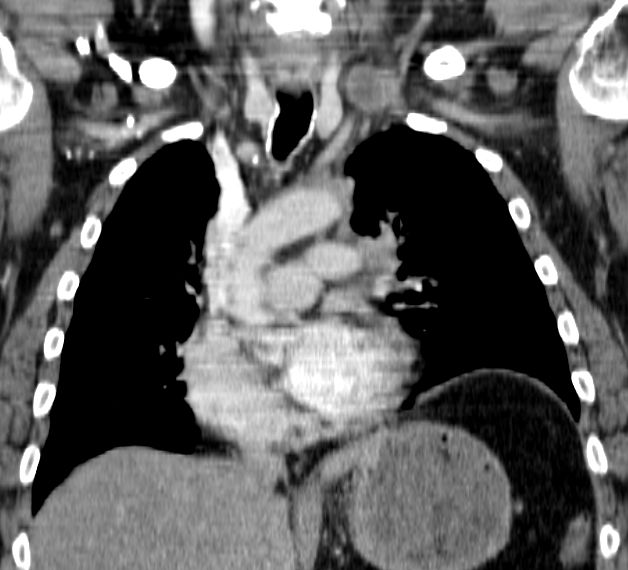

| Pancoast linker Oberlappen | 63-jähriger Mann mit einem Plattenepithelkarzinom

des linken Lungenoberlappens. Klinisch faustgroßes Vorwölbung über dem

linken Schlüsselbein.![]() |

Die Infiltrate haben die A. subclavia

eingeschlossen. Klinisch schlaffe Lähmung des linken Arm mit lividität.

Zusätzlich Verengung des Lidspaltes links.![]() | |